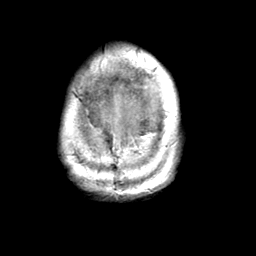

Meningioma, MR Study #1 -- Slice #21

[Home][Help][Clinical] Slice 21